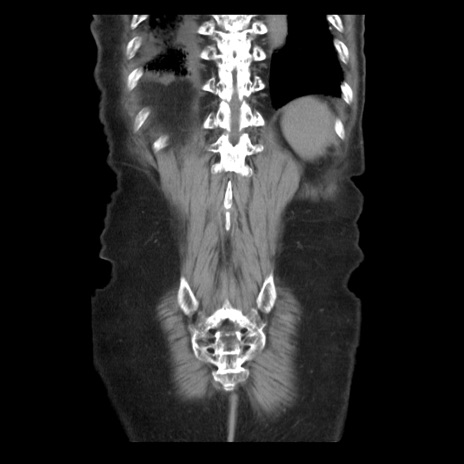

症例21(冠状断像)

【症例】70歳代男性

【主訴】腹痛

【現病歴】肝硬変・肝細胞癌にてかかりつけの方。約9時間前に食後より腹痛出現。症状が徐々に増悪し、嘔吐出現したため来院。

【既往歴】肝硬変、肝細胞癌(RFA、TACE後)

【身体所見】意識清明、表情苦悶様、BT 36℃、BP 129/78mmHg、P 88bpm、SpO2 97%(RA)、右上腹部から心窩部にかけて圧痛あり、反跳痛なし、筋性防御あり。

【データ】WBC 5800、CRP 0.16